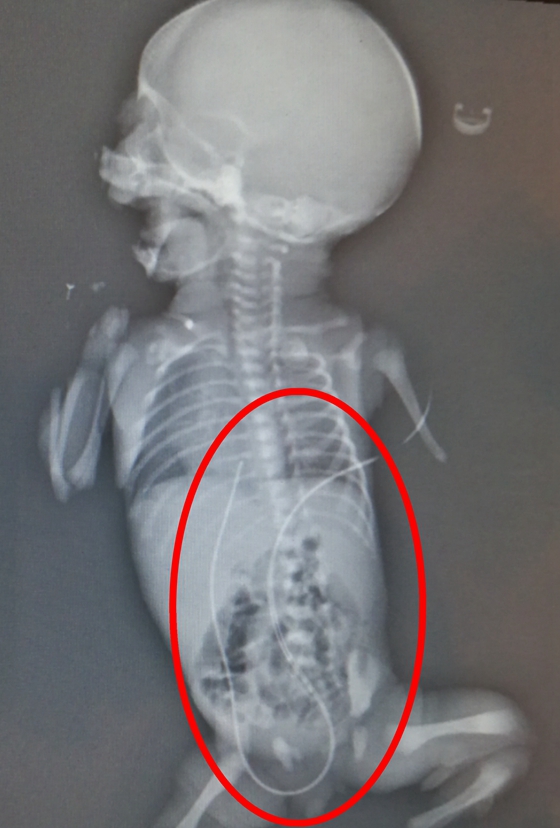

患儿出生后出现了呼吸急促、肤色紫绀、低血糖等表现,急需静脉通路输注抢救药物,且体重低下儿需长时间静脉营养支持,危在旦夕。在呼吸机辅助通气、温箱保暖等抢救措施稳定生命体征后,新生儿科团队立即给该患儿实施脐静脉置管术,过程顺利,导管内回血良好,术后X片提示导管位置正确。在出生后1小时内,救命的药物和营养液通过这根延续的“脐带”输送给了患儿,增加了抢救的成功率。目前,这根源源不断为患儿提供营养和抢救药物的脐静脉导管结束了它10天的使命,已顺利拔管。

医护人员为患儿成功插入脐静脉置管导管